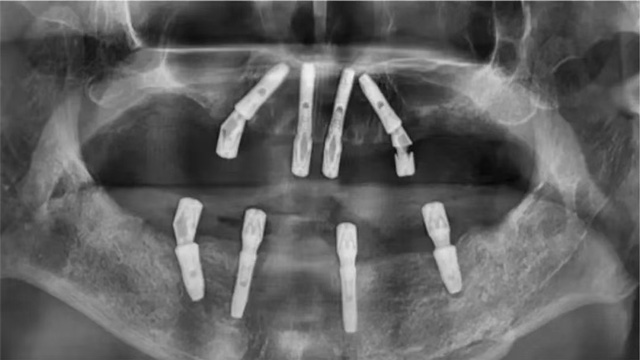

据新桥口腔成都蜀汉院区种植专科主任姜辰介绍,张先生的口腔情况较为复杂:之前种植的6颗种植牙牙冠全部脱落,只剩下种植体,其中一颗种植体已折断,还有两颗牙做过根管治疗,其中一颗牙冠脱落,此外,他口腔里还存在多颗牙齿缺失和松动等问题。

张先生10年前种下的6颗种植牙牙冠全部脱落

经过询问,医护人员得知张先生当年种完牙后,还没等到佩戴正式牙冠就离开成都了,他花“巨资”种下的6颗牙这么多年来只有临时牙冠。“临时牙冠是作为过渡使用的材料,在硬度、咬合、稳定性等方面都比不上正式的牙冠,影响到了种植牙的正常使用寿命。”牙冠脱落后,张先生继续使用仅剩下“光杆”的种植体进行咀嚼,最终导致种植体受损,发生折断、松动等情况。